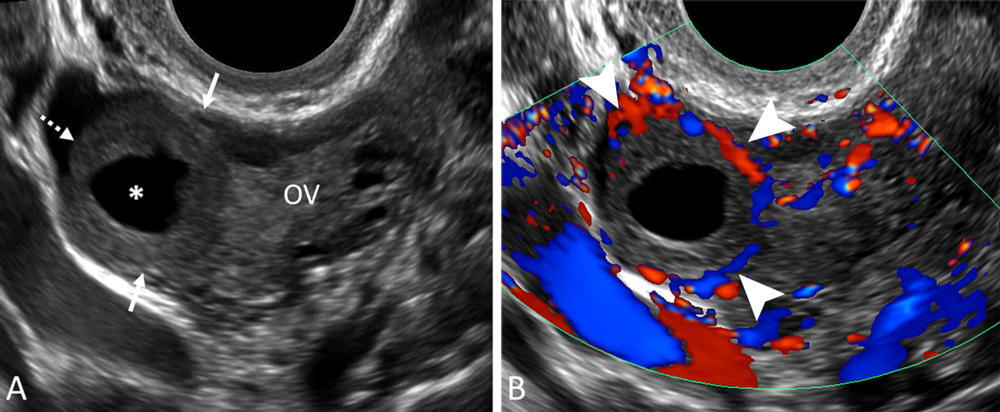

Figure 9. Corpus luteum. (A) Transvaginal sagittal grayscale and (B) color Doppler US image in a 31-year-old pregnant patient shows a round, hypoechoic, thick-walled structure (dotted arrow) with a central cystic space (*) and peripheral vascularity (arrowheads), characteristic of a corpus luteum. This corpus luteum arises in an exophytic fashion from the right ovary (OV), which can mimic a tubal ring of ectopic pregnancy. A helpful feature to diagnose a corpus luteum is a claw sign (solid arrows) of partially surrounding ovarian parenchyma, which confirms an ovarian origin.